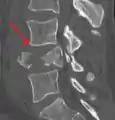

- A burst fracture of L4 as seen on CT